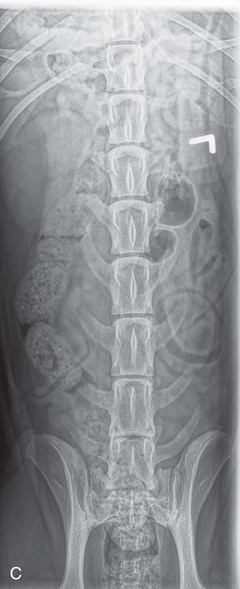

High-quality images are needed to see subtle changes in bone opacity, shape, and angulation of the vertebrae or vertebral column1,2 (Table 20.1). The common views of this portion of the axial skeleton are the lateral (L) and ventrodorsal (VD) views of the cervical, thoracic, thoracolumbar, lumbar, lumbosacral, sacral, and caudal vertebrae. Depending on the size of the patient, a full survey study is either four or five images of each orthogonal view.

MEASURE: Level of L1.

CENTRAL RAY: Level of L4 (palpate).

BORDERS: T12 to S1 (Just cranial to both the origin of the last rib and acetabulum).

13. To note symmetry on the VD lumbar radiograph of the Irish Wolfhound, you are looking for:

a. Superimposed intervertebral foramina that are of equal size

b. Superimposed pelvic limbs that are slightly positioned caudally

c. Spinous processes that are evident on the midvertebral body

d. A “Nike” swoosh created by the superimposition of transfer processes